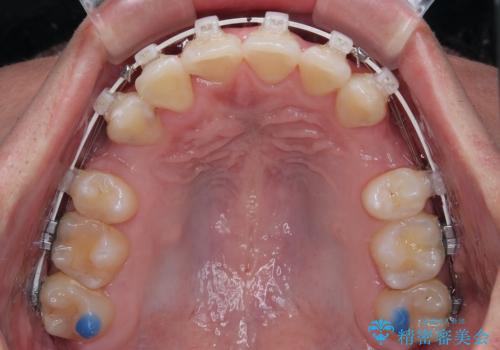

- 矯正装置

- 審美装置

叢生が強く、歯が並ぶスペースが不足していたため、

上下左右の第一小臼歯を抜歯して、矯正治療のための適切なスペースを確保する計画としました。